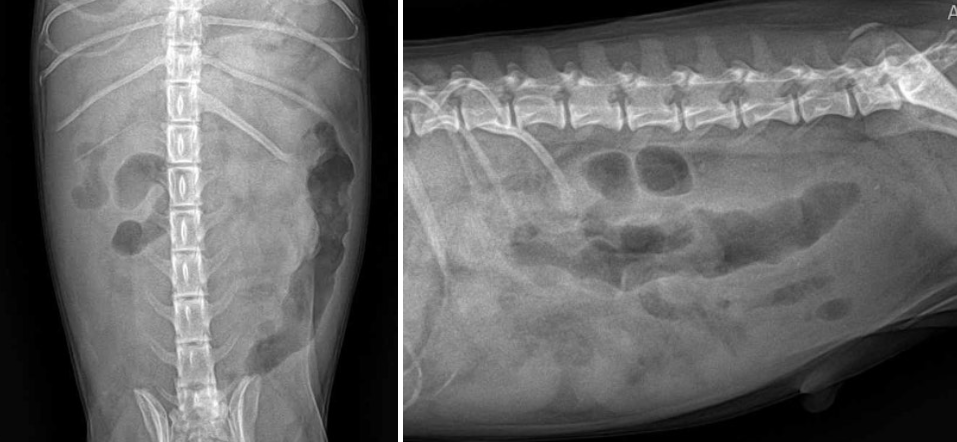

방사선 검사

방사선 검사

방사선 검사에서 복강 장기 윤곽이 흐릿하게 보일 정도의 복수가 확인되었으며, 하행 결장에는 가스가 차 있거나 묽은 변이 차 있는 모습이 관찰되었습니다.